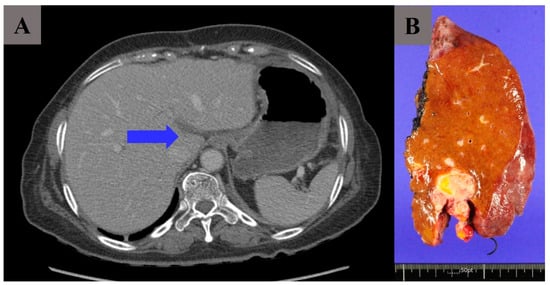

| Liver parenchymal invasion by preoperative imaging | |

| Yes | 3 (17.6%) |

| No | 14 (82.4%) |